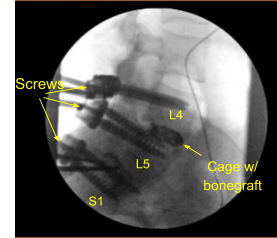

Transferred the data to the neuronavigation computer and image guided neuronavigation techniques were utilized for placement of the bilateral L4 pedicle screws which was accomplished by decorticating electric high-speed drill, cannulating the pedicles with the navigated pedicle finder, sounding for breaches, and measuring the depth using 5.5-mm tap and placing 6.5×45 mm titanium pedicle screws under neuronavigation guidance without difficulty. Neuromonitoring signals were table throughout.

Demineralized bone matrix allograft was placed into the interspace and then titanium expandable interbody device was placed under fluoroscopic guidance after sterilely draping the C-arm unit. AP and lateral imaging showed correct positioning and then the cage was expanded to the proper fit and the subsequent x-ray showed good positioning both in the midline and anteroposterior.

Next, a new CT scan was obtained, which showed correct positioning of the new pedicle screws and interbody spacer. Bilateral transverse processes of L4, L5, and lateral ala were decorticated for arthrodesis. Pre-cut, pre-contoured rods reflected and placed across the tulips from L4 to S1 and secured with locking caps and finally tightened with the torque and anti-torque device.